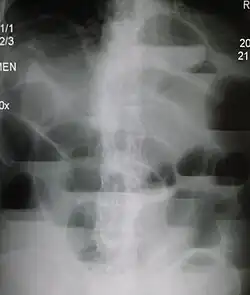

Causes of bowel obstruction include adhesions, hernias, volvulus, endometriosis, inflammatory bowel disease, appendicitis, tumors, diverticulitis, ischemic bowel, tuberculosis and intussusception.[1][2] Small bowel obstructions are most often due to adhesions and hernias while large bowel obstructions are most often due to tumors and volvulus.[1][2] The diagnosis may be made on plain X-rays; however, CT scan is more accurate.[1] Ultrasound or MRI may help in the diagnosis of children or pregnant women.[1]

Radiological signs of bowel obstruction include bowel distension (small bowel loops dilated >3 cm) and the presence of multiple (more than 2) air-fluid levels on supine and erect abdominal radiographs.[16] Ultrasounds may be as useful as CT scanning to make the diagnosis.[17]

Contrast enema or small bowel series or CT scan can be used to define the level of obstruction, whether the obstruction is partial or complete, and to help define the cause of the obstruction. The appearance of water-soluble contrast in the cecum on an abdominal radiograph within 24 hours of it being given by mouth predicts resolution of an adhesive small bowel obstruction with sensitivity of 97% and specificity of 96%.[18]